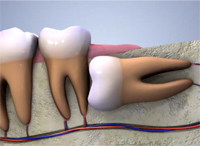

2. 斜めで前の歯にひっかかっている

|  |

隣の歯が虫歯になりやすくなります!

このような生え方の親知らずは前の歯に当たっていて、これ以上生えてくる事はありません!

周期的に歯茎が腫れたり、顎が痛くなったり、体調が悪い時・疲れがたまっている時に諸症状がでます。

放置しておくと、前の歯が根元付近で虫歯になり神経をとらないといけなくなったり、最悪抜歯になる事もあります!

この状態の親知らずが生えている方は早めに抜歯をお勧めします。

通常、他医院では大学病院や外科処置が出来る病院に行かないといけませんが、当医院では院長が外科出身ですので当医院での抜歯が可能です。